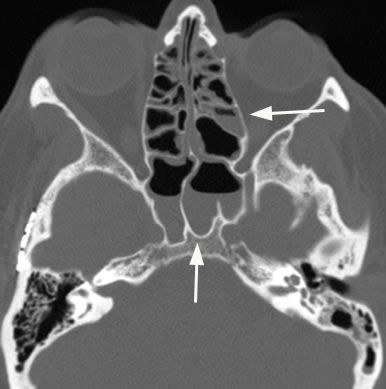

Axial image with arrow pointing to air-fluid level in maxillary sinus in acute sinusitis. Note the slightly bubbly appearing fluid.

Axial image demonstrating additional case of acute sinusitis with arrows pointing to air-fluid levels in the ethmoid and sphenoid sinuses.